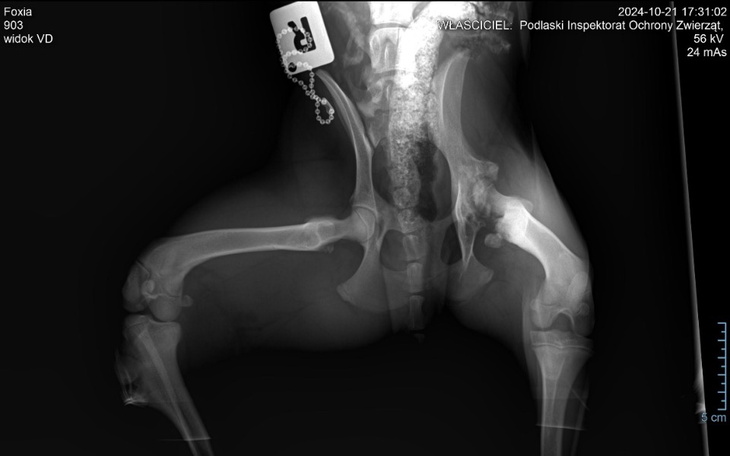

Niedawno pod naszą opiekę trafiła sunia, która została porzucona i zabrana z ulicy. Zaniepokoiła nas jej łapka – myślałyśmy, że to złamanie, więc szybko umówiłyśmy ją do ortopedy na rtg. Niestety, diagnoza jest przerażające. Okazało się, że nasza podopieczna ma schorzenie genetyczne, które wymaga pilnej operacji amputacji kości udowej. Choroba polega na aseptycznej martwicy głowy kości udowej. Dochodzi do niej, gdy zaburzony zastaje przepływ krwi od strony szpiku kostnego, od okostnej, a także innych naczyń.

Gdy dochodzi do zaburzenia osteogenezy, czyli tworzenia się i przebudowy kości w okresie intensywnego wzrostu organizmu, poprzez niedostateczne ukrwienie, pojawia się ognisko martwicy w jądrze kostnienia główki i szyjki kości udowej. Prowadzi to do zmian w strukturze kości, odwapnienie prowadzi do zmniejszenia wytrzymałości tkanki na urazy i prowadzi często do złamań, powstawania zmian anatomicznych takich jak spłaszczenie lub zniekształcenie głowy kości udowej. Zmiany te prowadzą do zapalenia stawu biodrowego, a rozwój zwyrodnienia generuje ankylozę stawu , praktycznie wyłączając go z funkcji. W zaawansowanych przypadkach wyczuwalne jest trzeszczenie podczas wykonywania ruchu, a chora kończyna staje się krótsza. W skrajnych przypadkach dochodzi do zaniku mięśni.